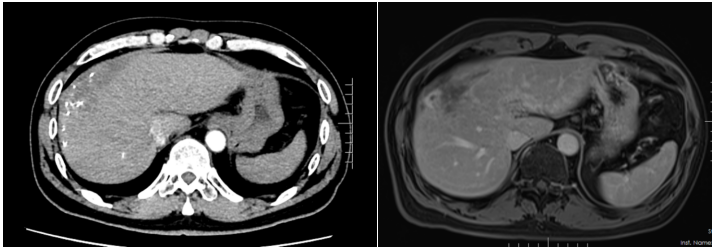

患者入院时诉说了自己与晚期肝癌对抗的痛苦与不易,同时也表明了与病魔抗争到底的决心。入院后,龙奎副主任医师立即为患者完善了CT、MRI+MRCP,ICG等检查,经过术前多学科MDT讨论后,认为患者肝癌转化效果满意,可以手术治疗。

由于患者肝癌位置特殊,肿瘤占据肝脏多个亚段,并且门静脉伴有海绵样变,手术中出血风险较大。另外,如大范围切肝,残余健全肝脏较少,术后有肝功能衰竭风险。为了保证患者手术质量安全,肝胆胰外科三病区高度重视,龙奎副主任医师组织科室详尽讨论了患者手术方案,在老专家孙敏教授、滕毅山教授、莫小华教授的鼎力支持下,最终决定采用腹腔镜微创手术方式完成手术,以最小的创伤让患者获得最大的收益。

手术中,由于患者有门静脉海绵样变特别容易出血,转化治疗后肝内管道走行变异,手术过程尤其艰难。龙奎副主任医师、董文志副主任医师、孙翊程医师与亚洲色吧 附二院优秀的麻醉团队、手术室护士团队通力合作,利用医院先进的荧光腹腔镜导航辅助,精准地完成了腹腔镜下肝IVb段+V段+胆囊切除术,历时5个小时,出血量200ml。